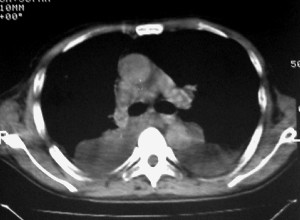

m ,60岁,右上肺ca术后一月。

纵隔淋巴结增大,双侧胸水。考虑术后残留,而非复发。

1、右肺癌术后改变。2、双侧胸水、腹水。3、多发性肝囊肿,右侧肾囊肿。

目前转移或复发的依据不足,术后才一个月,个人认为还是让临床去判断,而且需结合术前常规检查,有无肝肾囊肿;另外有一个疑问:肝胃间隙内团状软组织影是胃食管交接区吗,胃腔太小了吧,有无手术史请楼主告知.

肺癌术后 。双侧胸水 纵隔 胸膜 肝脏转移